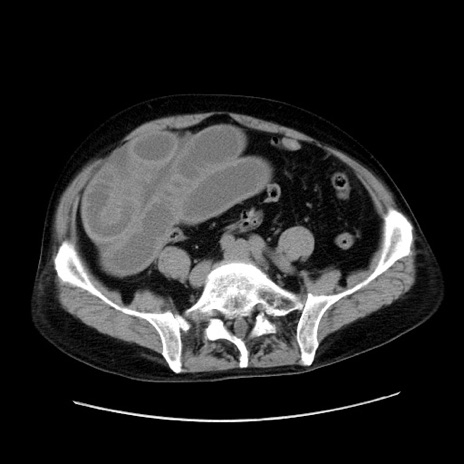

冠状断像

【症例】80歳代男性

【主訴】臍周囲痛

【現病歴】約6時間前から臍下部痛が出現。次第に腹部膨隆・背部痛も生じてきたため来院。背部痛の場所は変化しない。

【身体所見】意識清明、BT 36.3℃、BP  131/87mmHg、P 87bpm、SpO2 100%(RA)、臍周囲自発痛・圧痛あり、反跳痛なし、自発痛部位に一致して板状硬あり、腹部膨隆、腸雑音減弱、CVA tenderness両側陰性。

【データ】WBC 19600、CRP 0.33